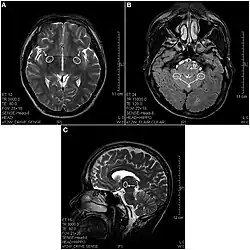

(A) T2-изображение отдела мозга, показывающее дегенеративные гиперинтенсивные пятна в базальном переднем мозге (показано стрелками). (B) T2-изображение, показывающее гиперинтенсивную дегенерацию в мозжечке (a) и в варолиевом мосту (b). (C) Сагиттальное T2-изображение, показывающее дегенеративные пятна в промежуточном мозге (таламус).

В 2013 году вышла статья в которой впервые были использованы МРТ-снимки при описании повреждений мозга у принимавших кетамин людей[3]. В выборке участвовали 21 человек со стажем употребления кетамина от 0,5 до 12 лет в дозах от 0,2 до 3 грамм ежедневно. Обнаружены многочисленные лезии во многих областях мозга появляющиеся после 2—4 лет употребления диссоциатива, а также атрофия коры во фронтальной, теменной и затылочной областях. Есть указания на то, что в результате воздействия кетамина многие структуры человеческого мозга могут получить хронические повреждения, отличные от повреждений от других психоактивных веществ воздействующих на ЦНС (например, кокаина, героина, метамфетамина)[3].